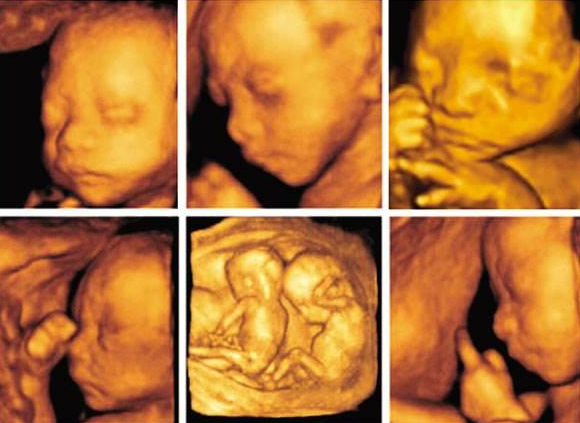

四維彩超四維彩超,有一些準媽媽可能會以為四維彩超就是彩色的,其實四維彩超并不是彩色,通過四維彩超報告單,準媽媽就可以看到,其實四維彩超多是土黃色的,但即使如此,準媽媽還是可以動態(tài)得看到胎寶寶的各種動作,比如吐舌頭、捂眼睛、伸懶腰、打哈欠等等。

四維彩超是目前最先進的超聲檢查技術,可以看到胎寶寶的動態(tài)畫面,從排畸效果來講,四維彩超在胎兒外觀和運動方面也可以看的更清晰,但專業(yè)的彩超醫(yī)生運用三維彩超也可以達到給胎寶寶排畸的效果。